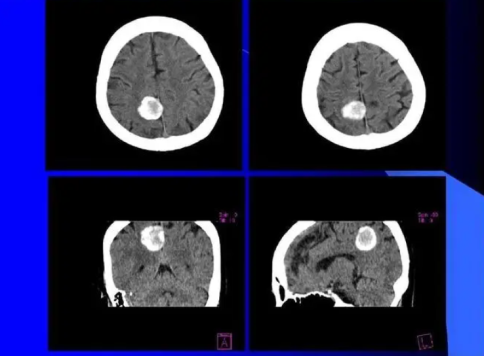

趙逸芳越來越愁悶,大概由于情緒的牽連,她又先后患上了尿路傳染、肛瘺、高血壓并且顱內(nèi)病變等多種重病。

先后被查出肛瘺、尿路傳染等肛腸重病,肌體嚴重受損,更因而夫妻生活不調(diào)諧造成被告煩悶,終極激發(fā)腦膜瘤。

可是,只有腦膜瘤的病因是不明確的,也不絕對和縫合針有直接聯(lián)系。